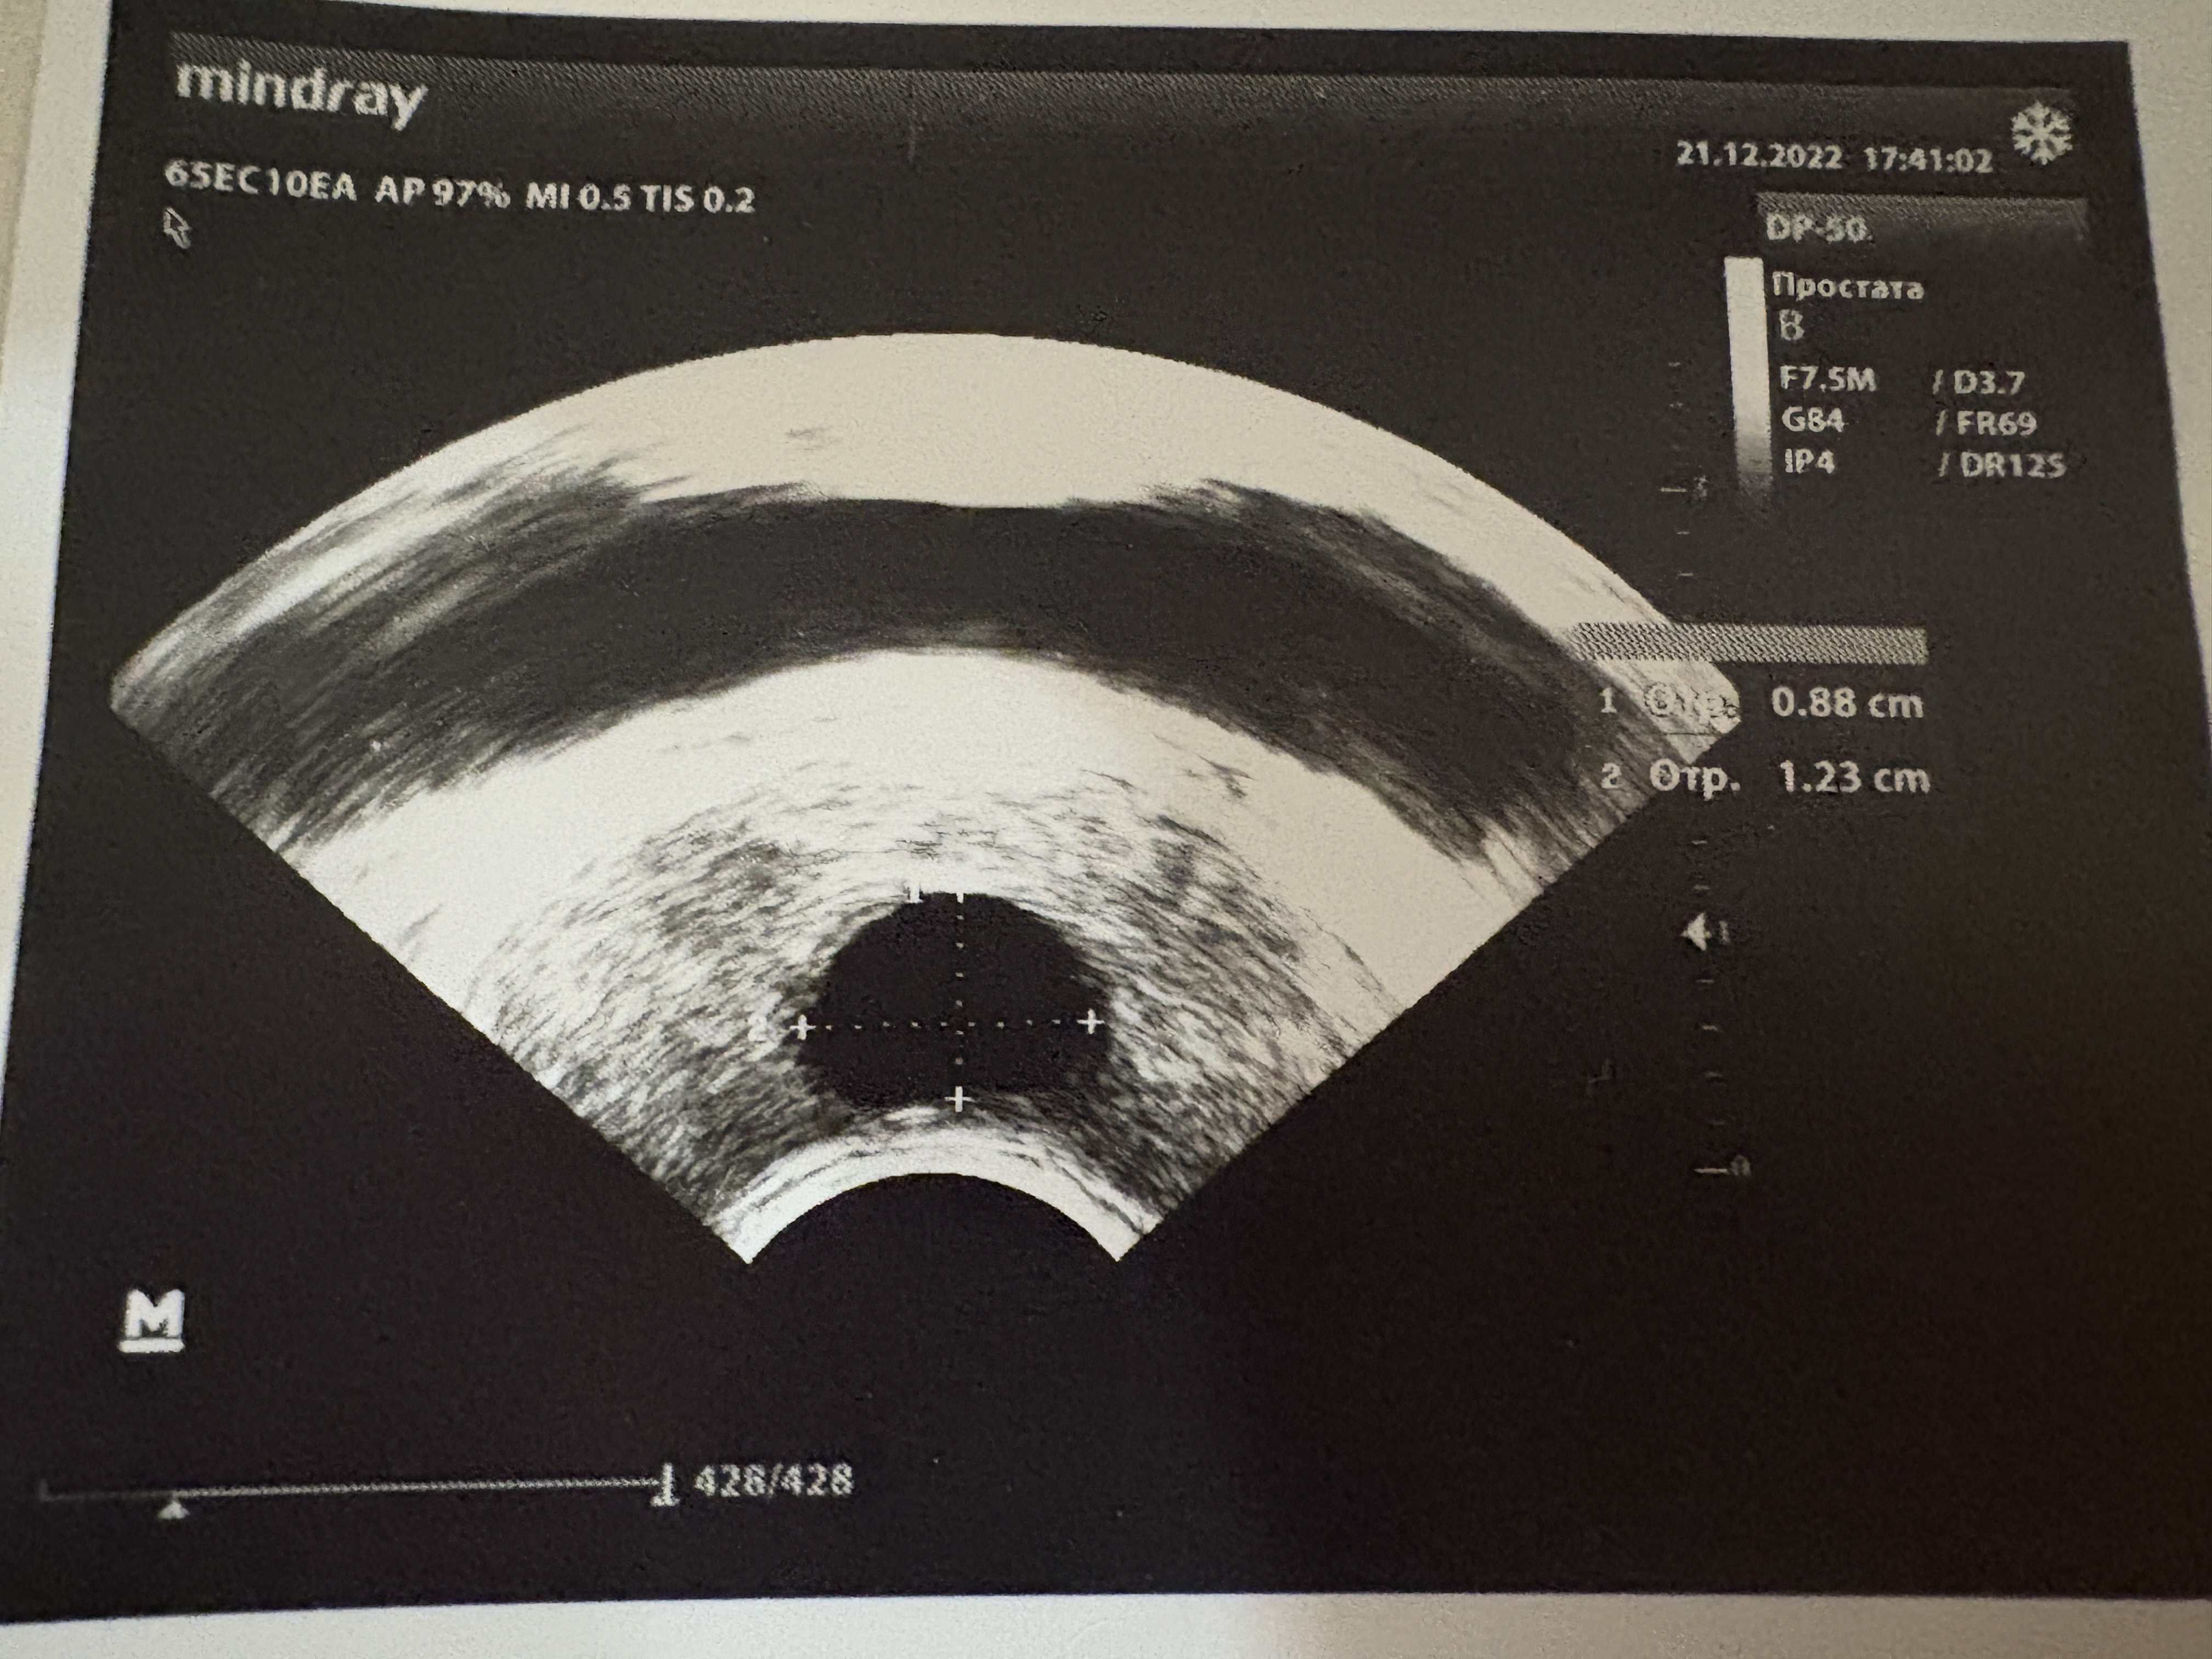

Был на Доплере без укола, узист сказал что приток слабый по правой стороне и есть тяжистость (сам не ебу что это) но говорит пока пиздеца не видит

возвращай к жизни эндокринку, я завтра сам иду сдавать анализы на 30 тысяч, с узи уже окончил

+ пиздуй делать УЗИ ДО лечения (СУКА НИКАКИХ УКОЛОВ ВСЕ БЕЗ УКОЛОВ ХУЕЛОВ ЧИСТО НА СПОКОЙНУЮ УЗИ) НОГ ХУЙ МАШОНКА ПЕЧЕНЬ ПОЧКИ И ЩИТОВИДКА

сдал все узи что мог

еще думаю простату смотреть ибо сука уверен есть простатит